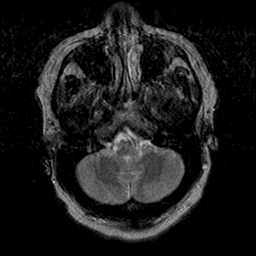

Cerebral hemorrhage, MR Study mr-t2 -- Slice #5

[Home][Help][Clinical] Slice 5